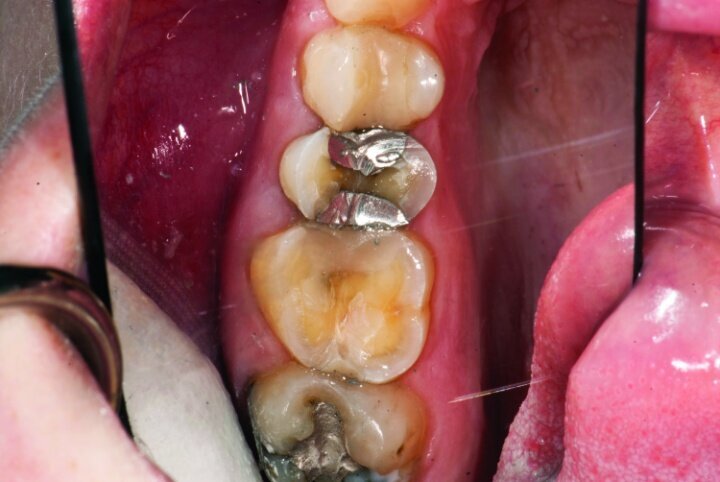

This patient presented for restorations of teeth #3 and #4 (Fig. 1a). Because of the size of the existing restorations, these teeth were diagnosed as structurally compromised (Figs. 1b, c). The prognosis without treatment was fair.

Gross occlusal reduction was completed using a KS7 bur to the depth cuts (Figs. 4–8b, 9c). Adequate clearance was verified with a 2 mm prep check from Common Sense Dental Products.

After gross occlusal reduction was completed, the remaining enamel ring was measured (Figs. 9a, b). The enamel rings were noted to be 1.5 mm, and the teeth were prepared for adhesively retained restorations. If the enamel rings were less than 1 mm, the teeth would have been prepared on the axial walls to create retention for cohesively retained crowns.

The remainder of the existing composite resin in #3 and the amalgam in #4 were removed. The occlusal surfaces of the preparations were blended into the interproximal areas using a KS2 bur to create smooth preparations (Figs. 10–15c). There was no retention or resistance form prepared to retain the restorations.